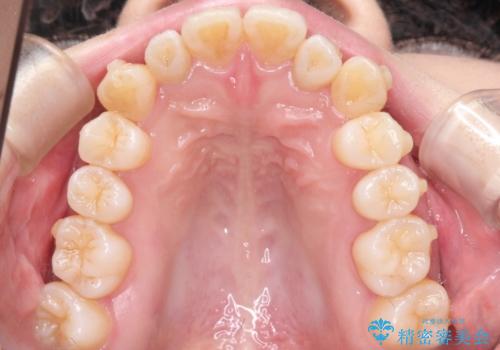

インビザラインで八重歯の矯正

- 八重歯を治したいとのことで、来院されました。

インビザラインにて、上顎の歯と歯の間をわずかに削り、並べる計画としました。

使用時間を守っていただけたので、比較的スムーズに矯正を終了することができました。